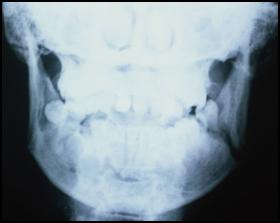

Fracturile mandibulei

etiologie: cauze traumatice, cauze patologice (infectii osoase, tumori osoase, distrofii si displazii);

zonele de rezistenta scazuta ale mandibulei: apofiza condiliana, zona unghiului, foramenul mentonier, zona parasimfizara la nivelul caninului, apofiza alveoloara;

clasificare:

partiale (rebord alveolar), totale;

unice, duble, triple, cominutive;

complete (cu interesarea periostului si deplasare), incomplete (in lemn verde);

dupa relatia focarului de fractura cu mediul extern (inchise, deschise).

Fractura de mandibula unghi stang (aspect radiografic, aplicarea tractiunilor elastice, imobilizarea intermaxilara rigida dupa practicarea osteosintezei in focar prin sutura osoasa cu fir de sarma)

Fractura mediana de mandibula imobilizata prin osteosinteza cu placute - consolidata - (indepartarea materialului de osteosinteza)